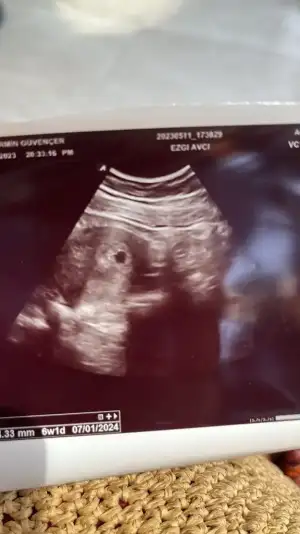

Selam canımcımlar benim bugün aşırı tansiyonum düştü ve miğdem bulandı doktora gittim istersen serum takalım dedi ben gerek yok dedim . Suyu az tüketirsek tansiyon düşermiş haberimiz olsun 🙈 günde en az 10 bardak su iç dedi 🙄 birde kesemiz doluymuş şükür ama perşembe günü 4+3 demişti bugün 6+1 dedi anlamadım bende sizinde öyle olmuşmuydu. Çok az kalp atışı aldı net duyamadım dedi cuma günü gel karından kalp atışını duymazsam vajinal bakarım dedi. Siz kaç haftalıkta duydunuz kalp atşını 🙈 birde melegim can melegim can karnımdan baktı ama daha erken mi cinsiyet için 🙈🙈

Yorumlayabilir misin acaba vajinal ultrason 6+5 🙏